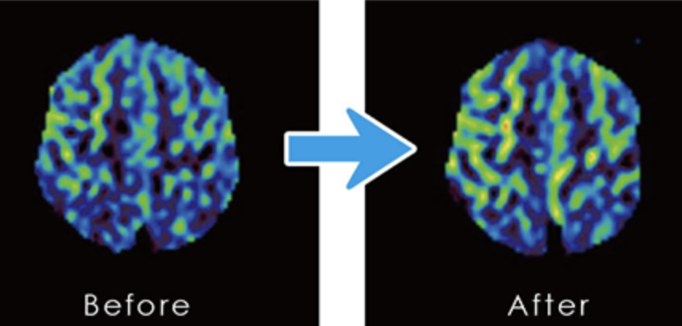

実験者6名をMRIにて脳血流を測定し、その後10分間脳大成理論のマインドテクノロジーを実践し再度MRIにて脳血流を測定しました。

その内3人の方の脳大成理論におけるマインドテクノロジー前後のCBF(脳血流)画像。

左が何もしない状態でMRI測定した写真(ビフォア)で、右が10分間マインドテクノロジーを実行してからMRI測定した写真(アフター)となります。

頭頂葉と側頭葉に血流増加が見られる。

以上の結果から、脳大成理論のマインドテクノロジーを実践することにより、脳血流が向上することが明らかになりました。講座・研修での体感・体験実験(ワークス)で実感できる変化や、脳大成理論に取り組んだ後に現実に表れた変化や成果のみならず、前に示したように確実に脳に変化が現れることが実証できました。